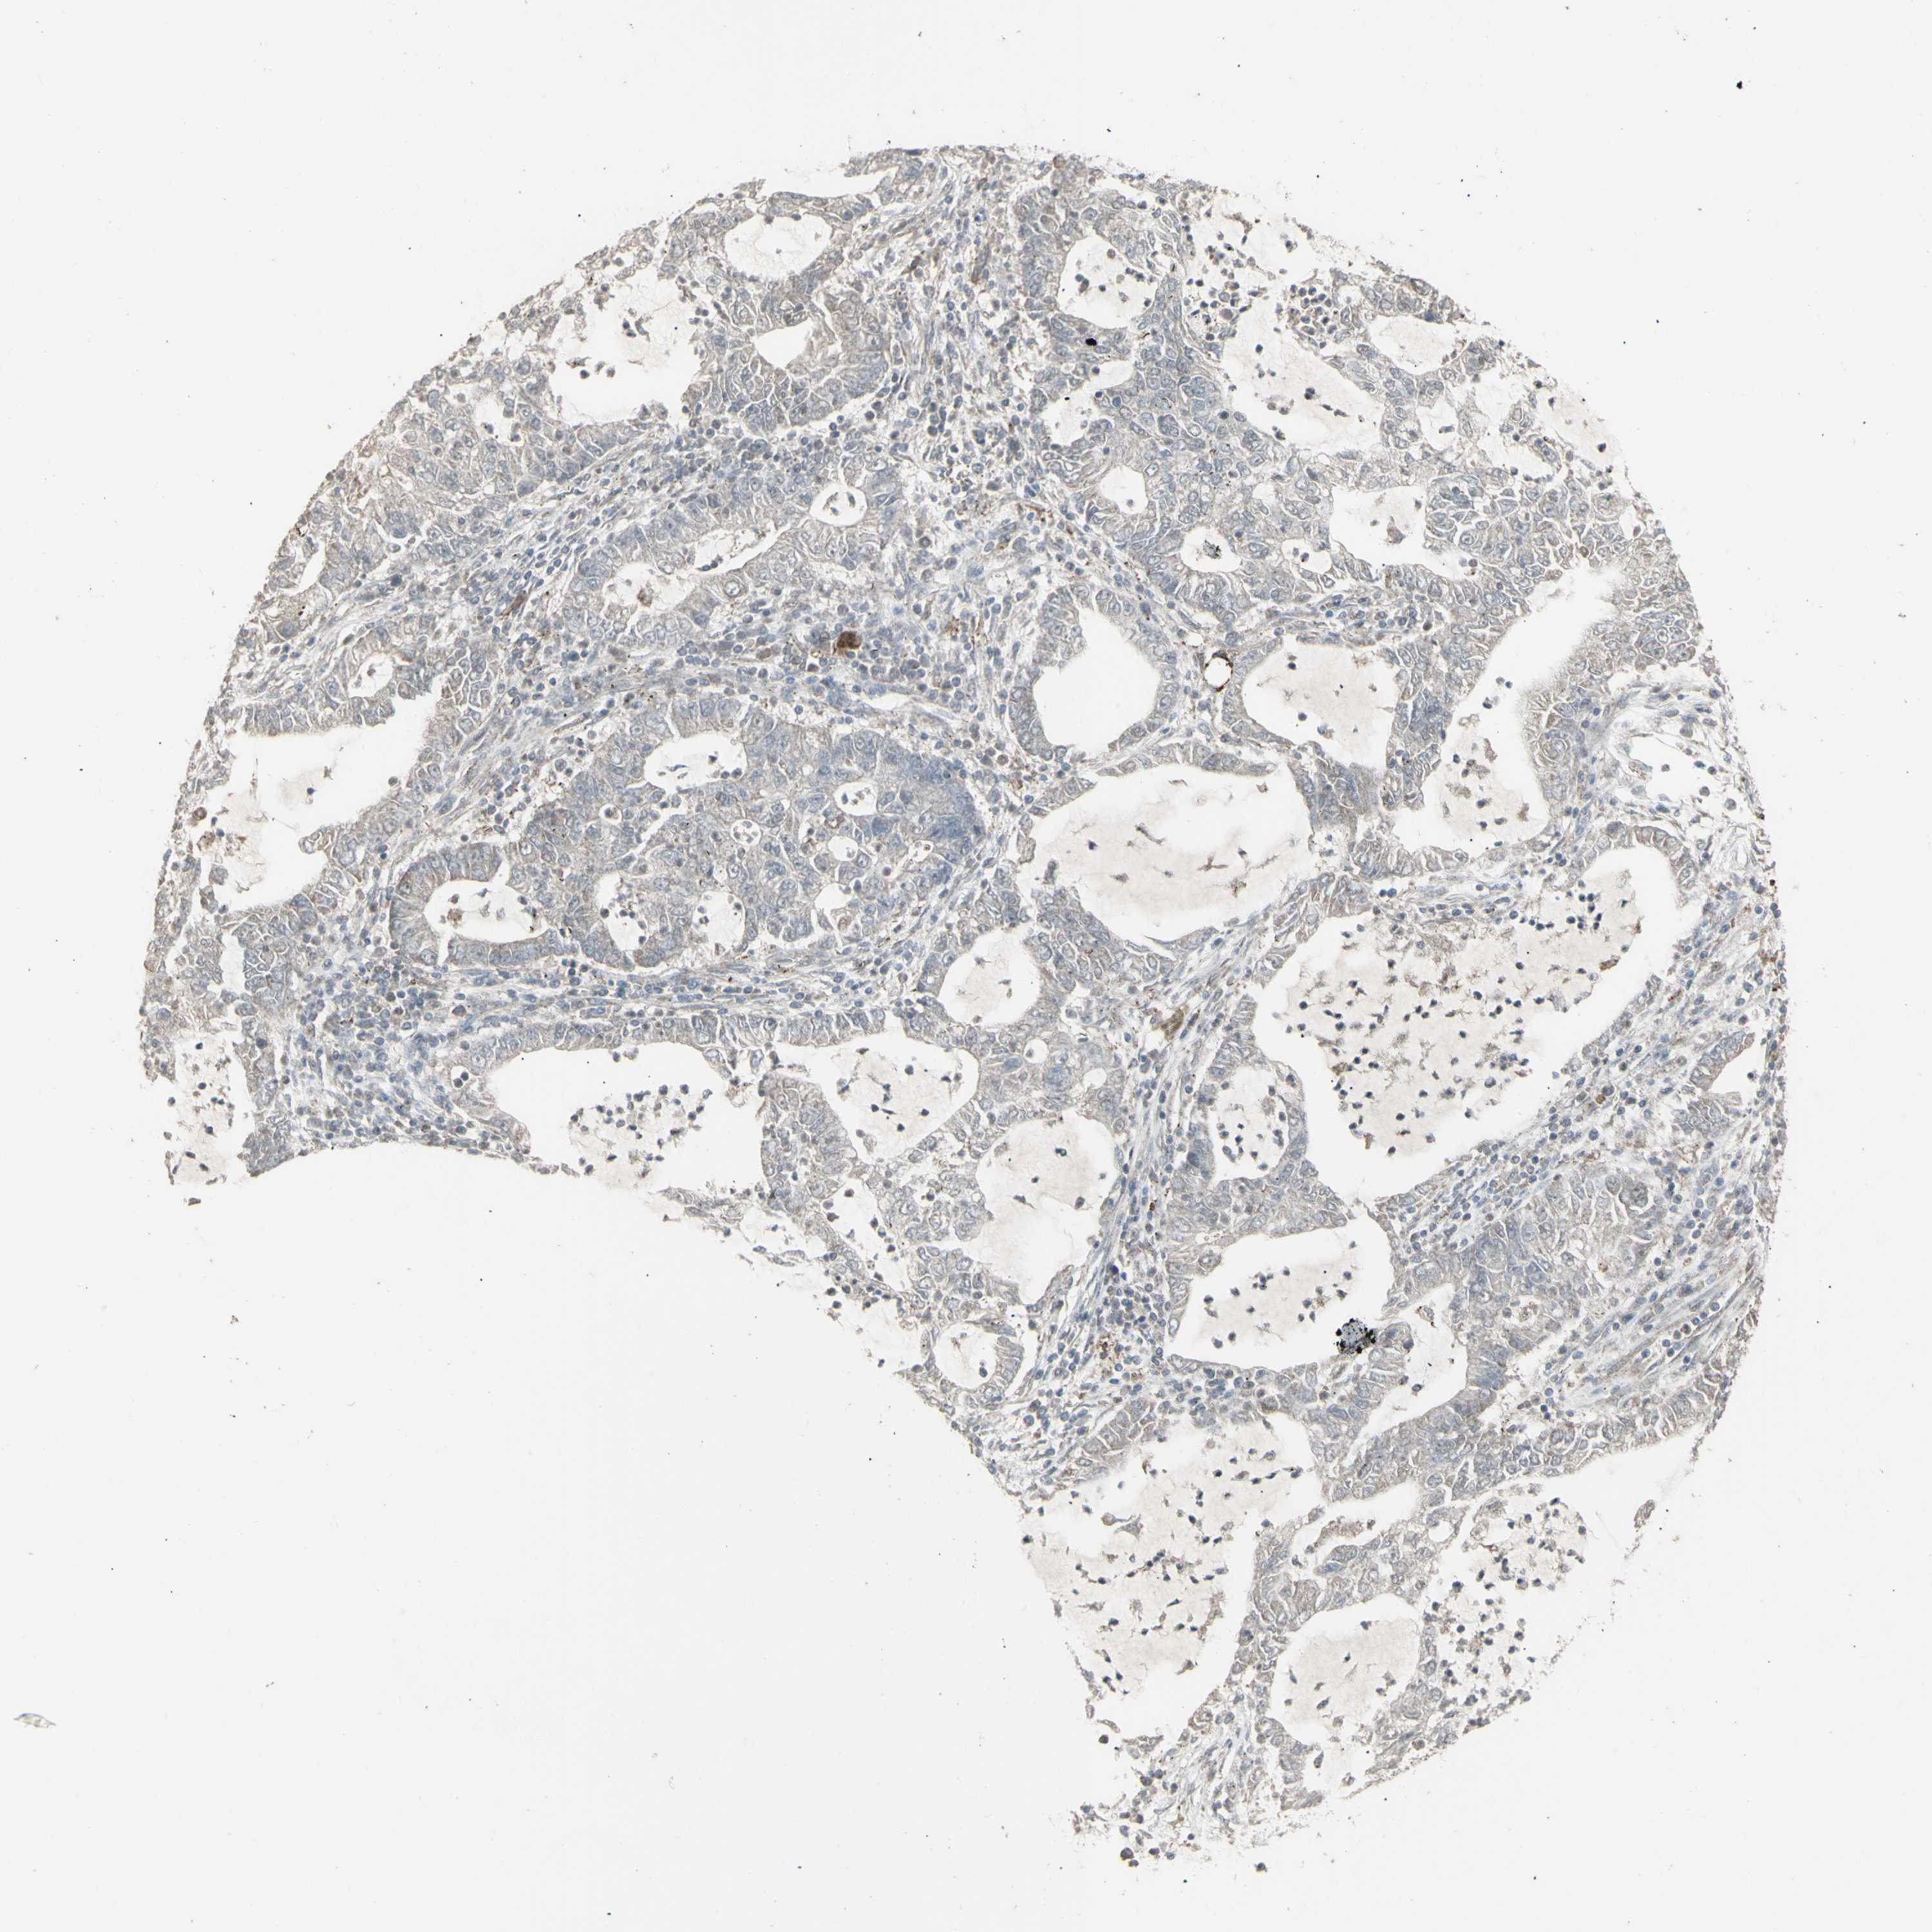

LUNG ADENOCARCINOMA (VALIDATION) - Interactive survival scatter ploti

The Survival Scatter plot shows the clinical status (i.e. dead or alive) for all individuals in the patient cohort, based on the same data that underlies the corresponding Kaplan-Meier plots. Patients that are alive at last time for follow-up are shown in blue and patients who have died during the study are shown in red.

The x-axis shows the expression levels (FPKM) of the investigated gene in the tumor tissue at the time of diagnosis. The y-axis shows the follow-up time after diagnosis (years). Both axes are complimented with kernel density curves demonstrating the data density over the axes. The top density plot shows the expression levels (FPKM) distribution among dead (red) and alive patients (blue). The right density plot shows the data density of the survived years of dead patients with high and low expression levels respectively, stratified using the cutoff indicated by the vertical dashed line through the Survival Scatter plot. This cutoff is automatically defined based on the FPKM cutoff that minimizes the p-score. The cutoff can be changed by dragging the vertical line or by entering a cutoff value in the square labeled "Current cut-off".

Under the Survival Scatter plot the p-score landscape (black curve; left axis) is shown together with dead median separation (red curve; right axis). Dead median separation is the difference in median mRNA expression between patients who have died with high and low expression, respectively. It is calculated as follows: median FPKM expression of dead patients with high expression - median FPKM expression of dead patients with low expression. This is intended to aid the user in visually exploring custom cutoffs and the associated p-scores and dead median separation.

Individual patient data is displayed and can be filtered by clicking on one or more of the category buttons on the top of the page. Categories describing expression level and patient information include: high, low, alive, dead, female, male and tumor stages. The scale of the x-axis can be toggled between linear and log-scale by clicking on the "x log" button. Mouse-over function shows TCGA ID, patient information and mRNA expression (FPKM) for each patient.

& Survival analysisi

Kaplan-Meier plots summarize results from analysis of correlation between mRNA expression level and patient survival. Patients were divided based on level of expression into one of the two groups "low" (under cut off) or "high" (over cut off). X-axis shows time for survival (years) and y-axis shows the probability of survival, where 1.0 corresponds to 100 percent.

RNASEL is not prognostic in Lung Adenocarcinoma (validation)

Best expression cut offi

Based on the FPKM value of each gene, patients were classified into two groups and association between prognosis (survival) and gene expression (FPKM) was examined. The best expression cut-off refers the FPKM value that yields maximal difference with regard to survival between the two groups at the lowest log-rank P-value. Best expression cut-off was selected based on survival analysis .

When clicking on this number, the vertical dashed line indicating cut-off, the interactive survival plot, and the Kaplan-Meier curve will be adjusted to show results based on the best expression cut-off.

: 13.17

P scorei

Log-rank P value for Kaplan-Meier plot showing results from analysis of correlation between mRNA expression level and patient survival.

N/A

TCGA RNA samplesi

RNA-seq data is reported as average FPKM (number Fragments Per Kilobase of exon per Million reads), generated by the The Cancer Genome Atlas (TCGA) .

Normal distribution across the dataset is visualized with box plots, shown as median and 25th and 75th percentiles. Points are displayed as outliers if they are above or below 1.5 times the interquartile range. FPKM values of the individual samples are presented next to the box plot.

Average pTPM 11.9

Number of samples 105